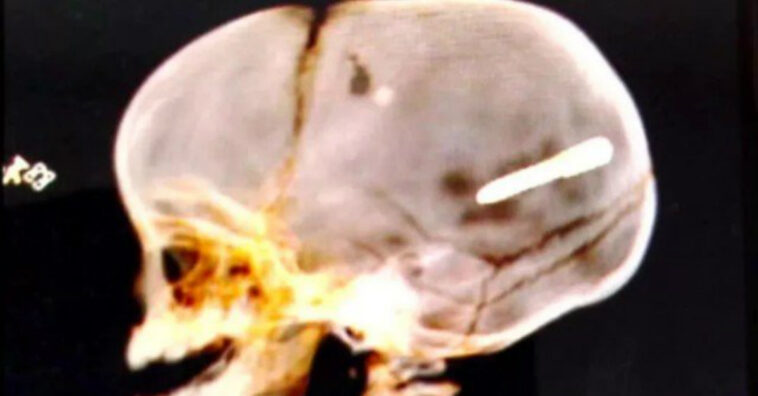

O pequeno Walace Martin dos Santos foi atingido por um parafuso lançado por uma pistola de fixar gesso. Não se sabe quem foi o autor do disparo, mas a polícia procura por informações. Também não se sabe se o disparo foi acidental, intencional ou somente uma brincadeira que terminou da pior forma.

Ele foi encaminhado para o posto de saúde mais próximo e depois transferido imediatamente para o Hospital Pedro II, onde foi prontamente atendido. Lá, passou por apenas uma cirurgia, trazendo um alívio temporário para futuras medidas. Devido a localização do prego, eram necessários mais recursos para o procedimento.

O que se tem de concreto é a morte de um bebê inocente e pais inconsoláveis. Uma das avós do pequeno Wallace afirmou que, ao chegar, ele foi operado para reduzir a pressão intracraniana, porém sem sucesso quanto a retirada do corpo estranho. Em seguida, ele foi encaminhado para a UTI, onde foi estabilizado por equipamentos e remédios.